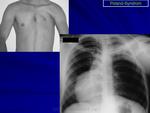

Поланда синдром (Poland syndrome)

Синдром Поланда (СП) представляет собой комплекс пороков, включающий отсутствие большой и малой грудной мышц, синдактилию, брахидактилию, ателию (отсутствие соска молочной железы) и/или амастию (отсутствие самой молочной железы), деформацию или отсутствие нескольких ребер, отсутствие волос в подмышечной впадине и снижение толщины подкожно-жирового слоя. Отдельные компоненты этого синдрома впервые были описаны Lallemand LM (1826) и Frorier R (1839). Однако назван он по имени английского студента-медика Alfred Poland, который в 1841 году опубликовал частичное описание данной деформации. Полную характеристику синдрома в литературе впервые опубликовал Thompson J в 1895 году.